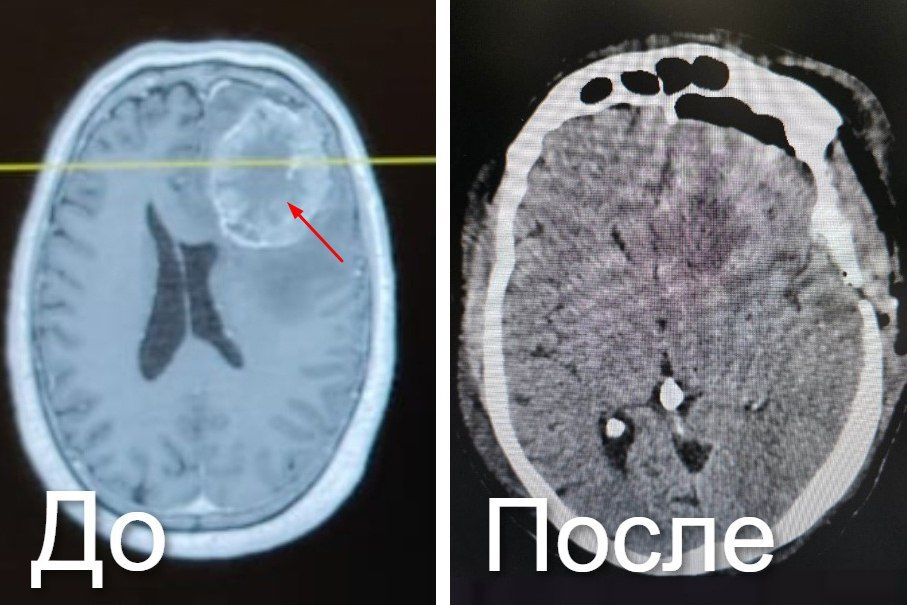

Образование появилось от метастаз рака прямой кишки. С 2019 года выросло больше куриного яйца. Вызывало боль, тошноту, потерю координации.Врачи провели ювелирную операцию. Ушло 5,5 часов. Использовали хирургический микроскоп и нейронавигационную...